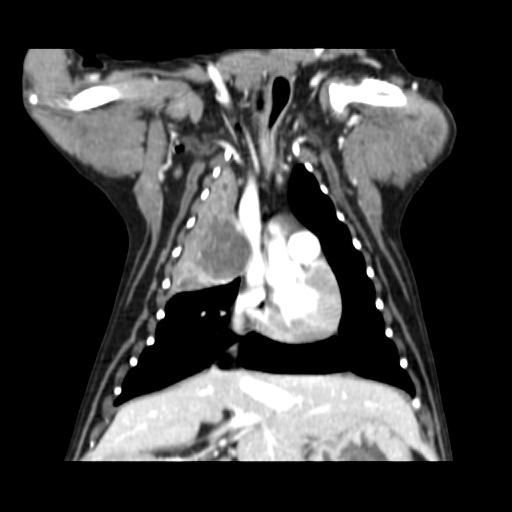

엑스레이 사진과 CT 사진(흉부 앞, 우측 옆)은 첨부하였습니다.

폐 우측 위쪽에 원발성 암이 발생한 것으로 보였습니다.

식도와 심장을 눌러서 기침을 발생시켰습니다.

나쁜 소식은 심장과 혈관이 위치한 안 좋은 부위에 암이 있다는 것이고,

좋은 소식은 심장과 혈관과 아직 붙지 않고 떨어져 있다는 것이었습니다.